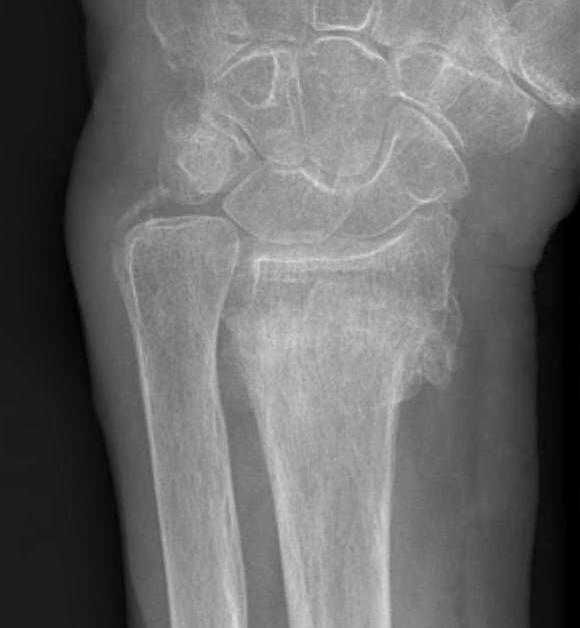

Xray

Bilateral xrays

PA film in neutral

- wrist neutral

- elbow & shoulder at 90°

Malunion

| Radial shortening | Radial inclination | Positive ulna variance |

| Dorsal tilt > 15 degrees | Volar tilt > 10 degrees | Articular step > 3 mm |